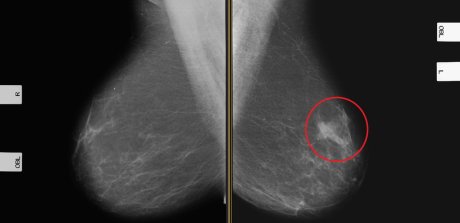

rak dojke Neki suplementi utiču negativno utiču na hormonalnu terapiju Foto: Shutterstock